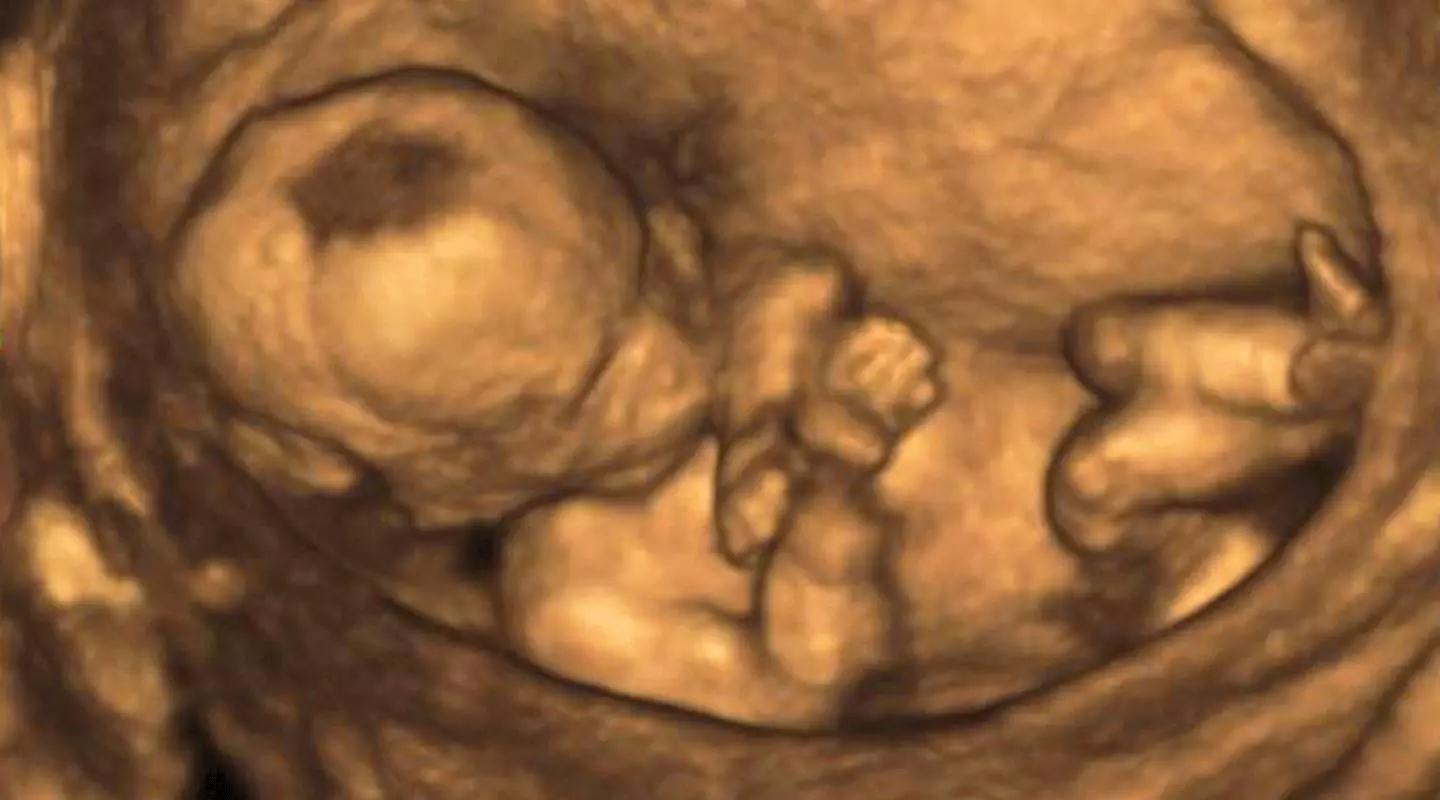

超声影像(基础版四维彩超)